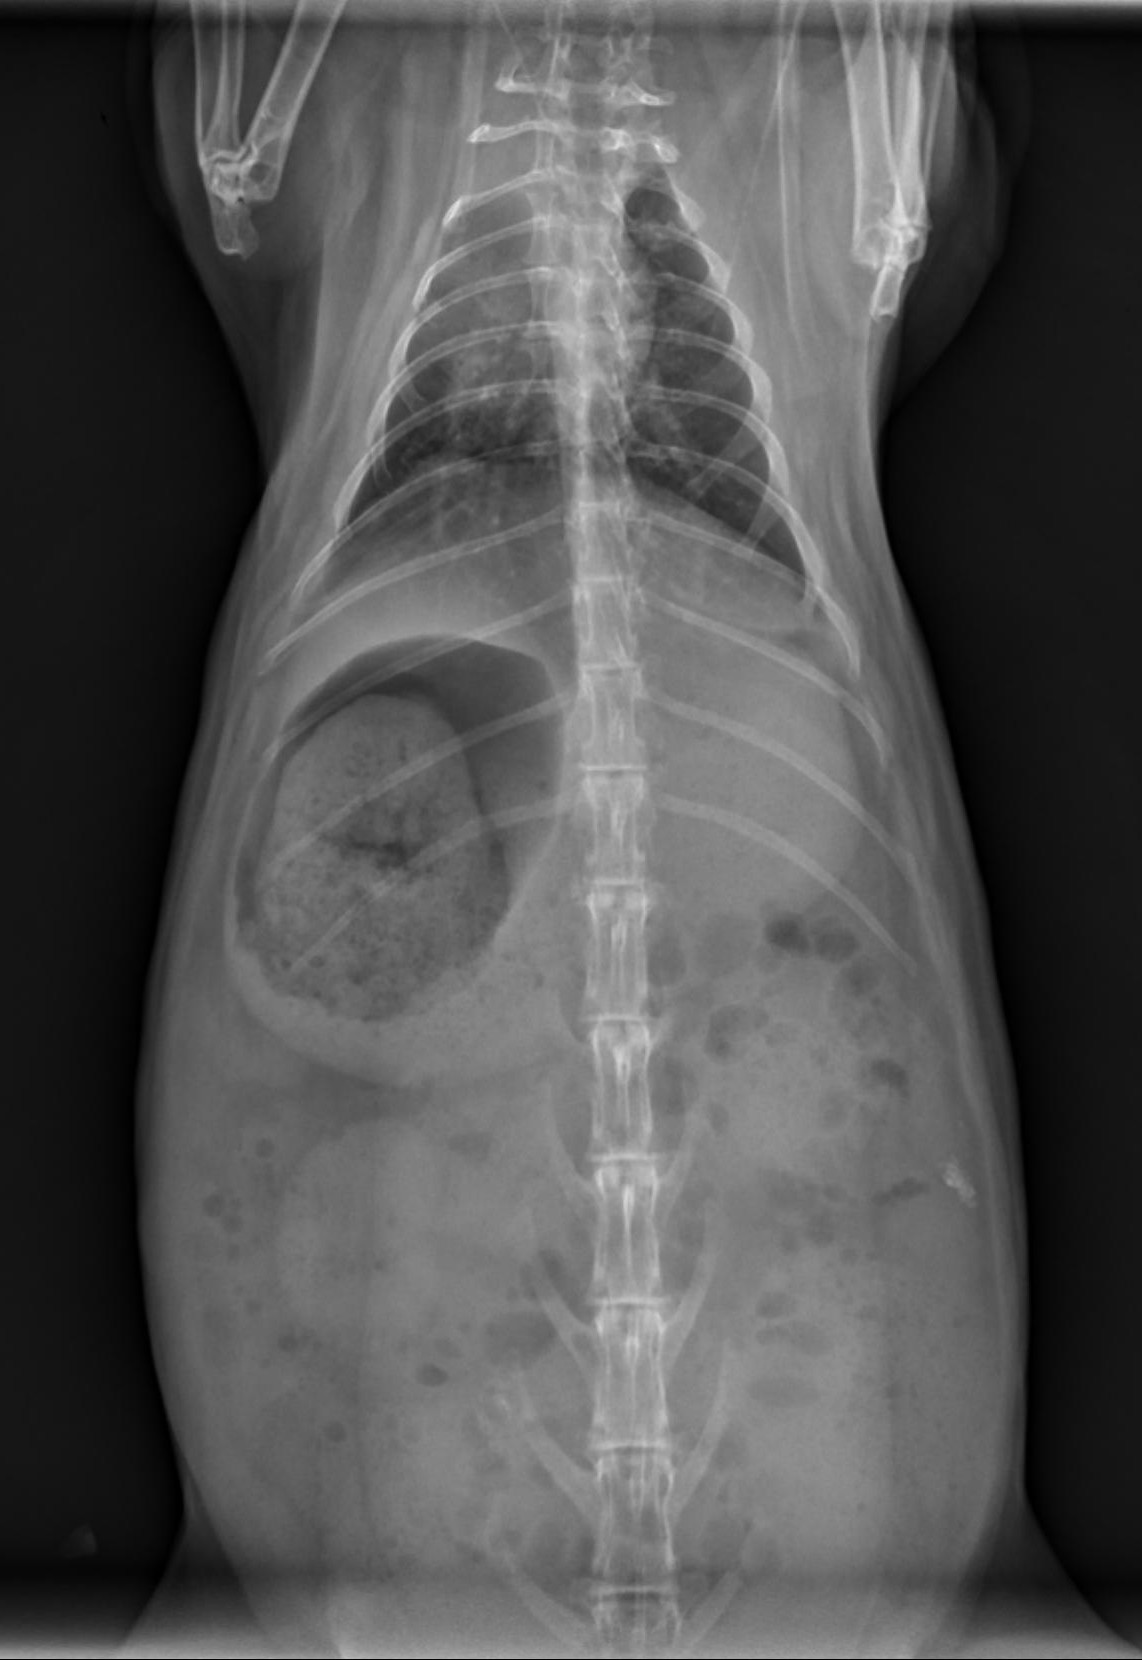

Radiographic Patterns: Ileus vs. Gastric Outflow Obstruction

Radiographs can help differentiate between RGIS and a potentially more serious gastric outflow obstruction (although to be honest, I approach treatment the same way for both in the first 24 hours).

RGIS radiographic signs:

• Dehydrated, radiodense stomach contents

• Circumferential line of gas around dehydrated contents

• +/- cecal distension

Gastric outflow obstruction:

• Enlarged, fluid-filled stomach

• Dorsal gas cap

• Stomach extends beyond last rib

• 2 populations of small intestine often present